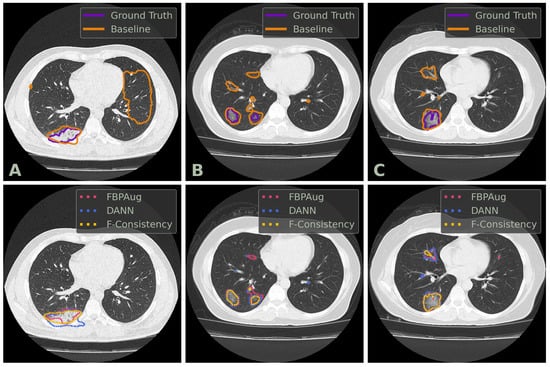

We conclude the comparison of the methods with the qualitative analysis. In Figure 2, one could find examples of the Baseline, FBPAug, DANN, and F-Consistency predictions on the COVID-test dataset and compare them with the ground truth. Although all adaptation methods perform similar to the ground truth with minor inaccuracies, Baseline outputs the massive false positive predictions on the unseen domain. Additionally to the quantitative analysis above, the latter observation highlights the relevance of the domain adaptation problem in the COVID-19 segmentation task.

Figure 2. Examples of axial CT slices from the COVID-test dataset with the corresponding predictions and ground truth annotations. Three columns, denoted (AC), contains three unique slices. The top row contains the contours of the ground truth and baseline prediction. The bottom row contains the contours of the adaptation methods’ predictions. DANN and F-Consistency correspond to DANN and F-Cons from Table 3, respectively.